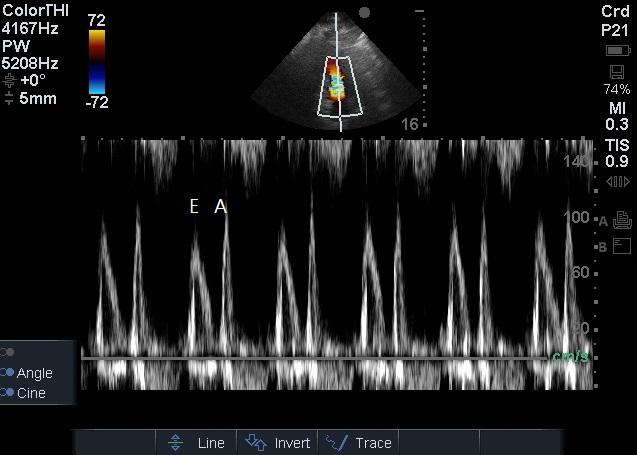

1.2 方法患者入院24 h内完成心脏超声检查。患者左侧卧位,以能显示心尖四腔心切面及五腔心切面为准,以美国Sonosite公司Edge超声诊断系统相控阵探头经心尖对患者二尖瓣、LVOT进行评估,彩色多普勒显示血流束,脉冲型频谱多普勒测量二尖瓣E峰流速及LVOT峰值流速(图 1~2),连续显示多个呼吸周期,选取呼吸周期内血流速变化规律波形,测量血流速最大值及最小值,重复以上过程,每个测量部位血流速共测量三组最大值及最小值,然后计算平均数。二尖瓣E峰流速呼吸变异度=(二尖瓣E峰流速最大值-二尖瓣E峰流速最小值)/[(二尖瓣E峰流速最大值+二尖瓣E峰流速最小值)/2],LVOT峰值流速呼吸变异度=(LVOT峰值流速最大值-LVOT峰值流速最小值)/[(LVOT峰值流速最大值+LVOT峰值流速最小值)/2][1]。

| 图 1 LVOT频谱多普勒检查 Figure 1 LVOT Doppler examination |

| 图 2 二尖瓣频谱多普勒检查 Figure 2 Mitral valve spectral Doppler examination |